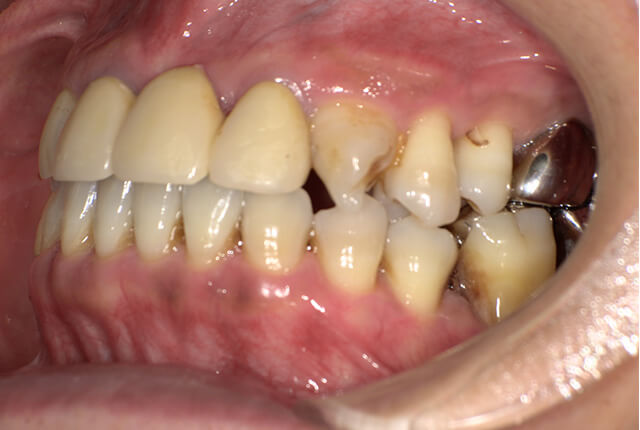

| 主訴 | 噛めない、食事がしっかりできる様になりたい。 |

| 診査診断 | 歯周病、歯の崩壊、不良補綴。 全顎的咬合異常、前歯の噛み合わせ、奥歯の噛み合わせに問題あり。 |

| 治療計画 | 欠損部インプラント 不良補綴のやり直しと欠損部インプラント。 咬合の再構築、なるべく歯を残せる様に治療計画を立案。 |

| 治療期間 | 6ヶ月 |

| 費用 | 290万円 |